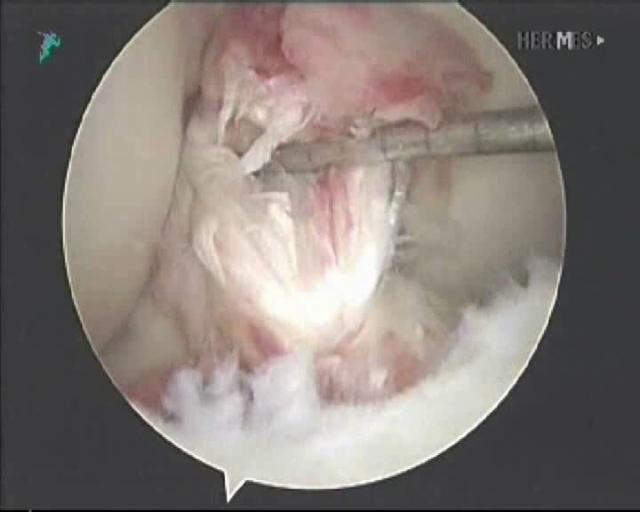

断裂的前交叉韧带(关节镜下视图)

2、关节液浸泡吸收。膝关节里面尤其是髁间窝这个位置相对来说是比较,如果说前交叉韧带断了相对来说比较空旷的,这个时候断了之后也没有一个比较明确的附着点,同时关节液里面有大量的液体,泡着前交叉韧带,时间长了(一般来说一个月左右),前交叉韧带断裂后就给吸收掉了,就消失了。